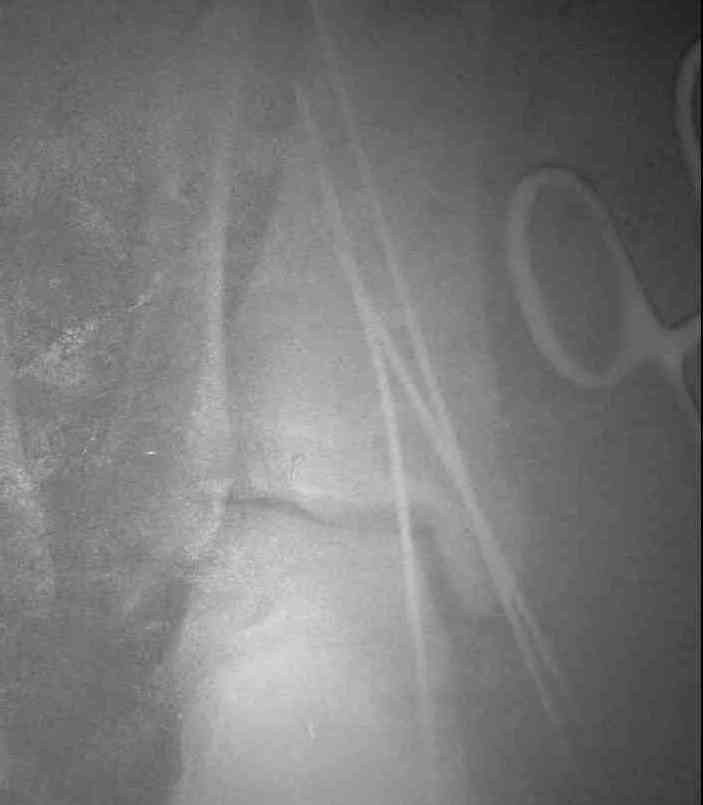

Уважаемые коллеги! Хотел-бы продолжить разговор об исходах переломо-вывихов в голеностопном суставе. При этом, в данном конкретном случае, хотелось узнать мнение опытных коллег об эндопротезировании. На консультацию обратилась пациентка, 26лет. В 2002 году открытый переломо-вывих. Лечение: вправление, трансфиксация спицами и гипсовая повязка. Около 4-х месяцев сохранялись явления нагноения вокруг спиц. На сегодня - движения в суставе отсутствуют, постоянные боли, функциональное укорочение конечности = 3 см. На недавней конференции по хирургии стопы и голеностопного сустава демонстрировался эндопротез НИИТО им. Вредена, внешне понравился. Юрий Алексеевич Булахтин